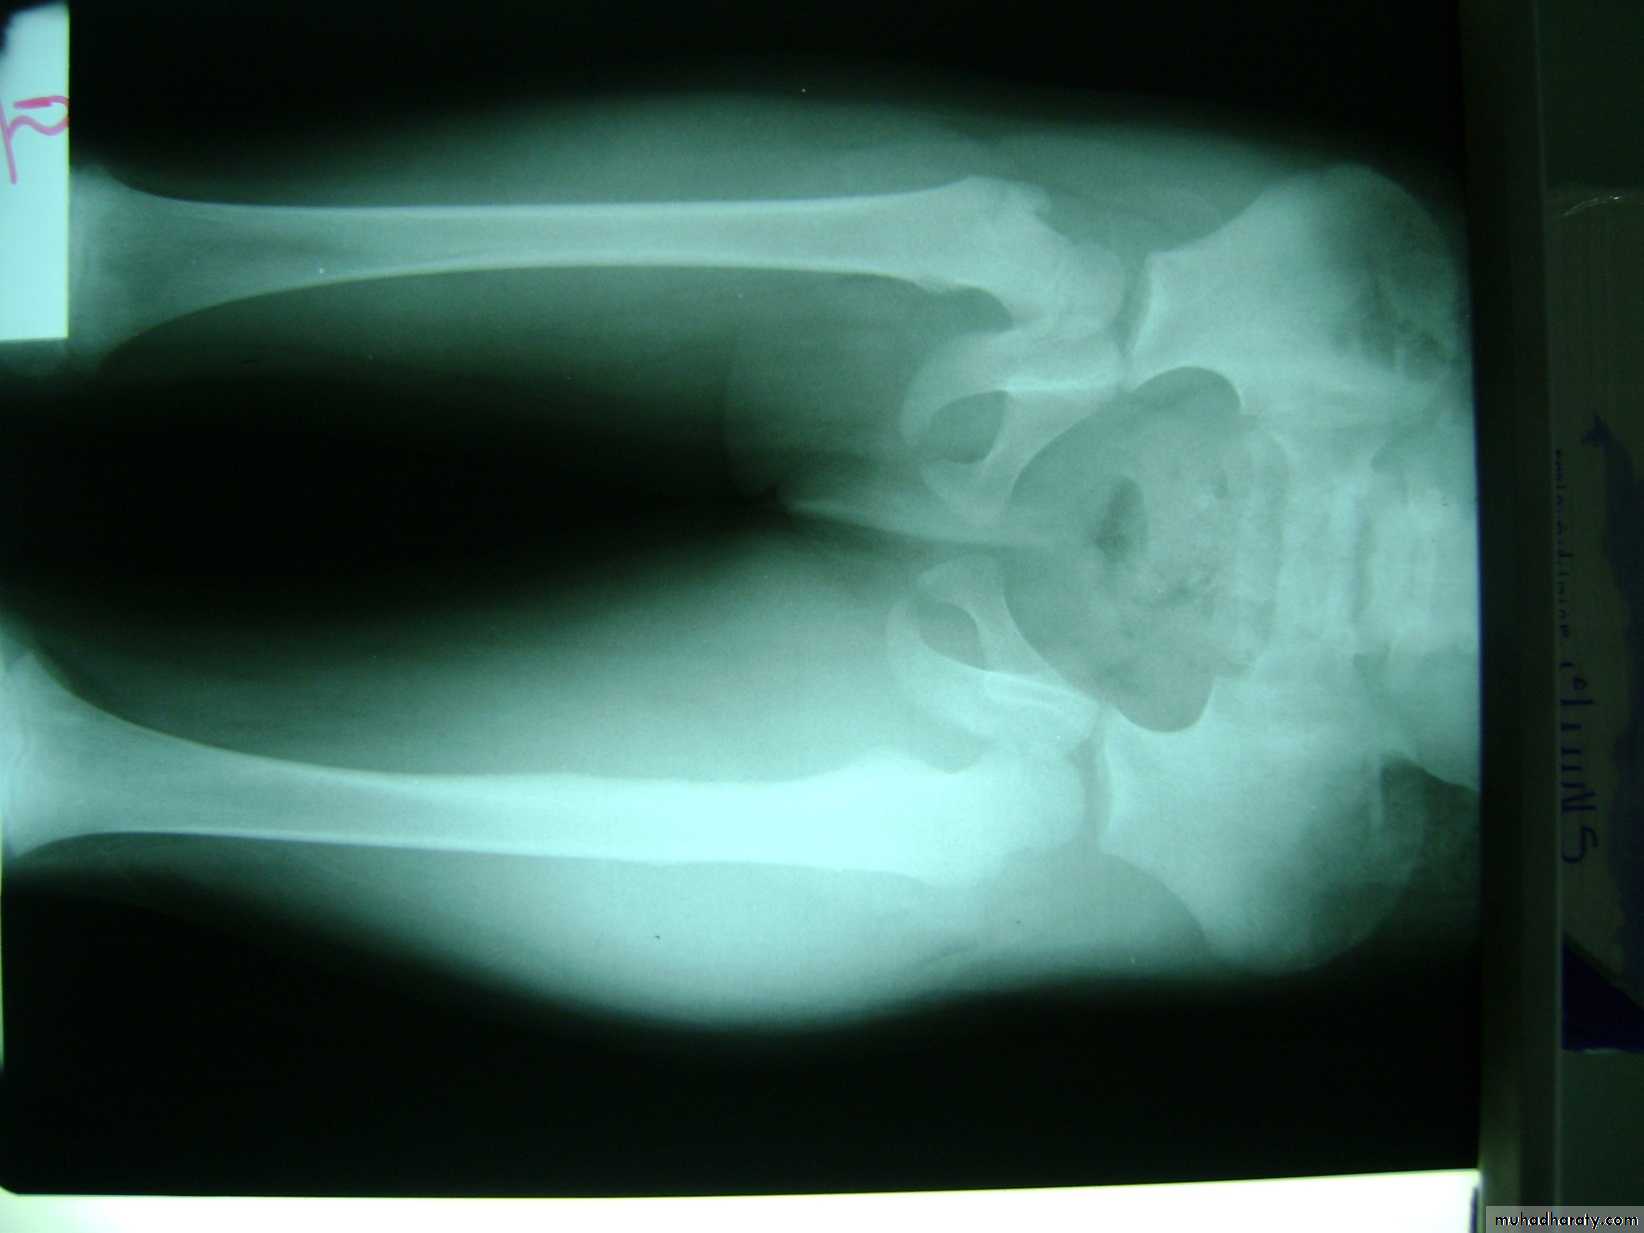

Large lesions may have a ‘cauliflower’

appearance, with degeneration and calcification in the Centre of the cartilage cap.30

is pathognomonic. There is a

well-defined exostosis emerging from the metaphysis,its base co-extensive with the parent bone.

It looks smaller than it feels because the cartilage cap is usually invisible on x-ray.

The x-ray appearance